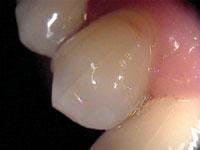

Radiographs usually are not helpful in the detection of cracks. They tend to be unremarkable in most cracks, because these fractures usually run mesiodistally and are not in the plane of the X-ray beam. Sometimes, however, the presence of a complete vertical root fracture can be seen radiographically (see Figure 2). These are cases where the crack extends beyond the crown of the tooth and down into the root. Here you may see a radiolucency involving the lateral aspect or halo surrounding the entire root. This can be differentiated from other radiolucencies by the fact that it surrounds the root uniformly, rather than being located at the portal of exit of the apical foramen or lateral canal. These cases are usually associated with a probing depth corresponding to the extent of the crack. This is the case when the crack is more extensive, long-standing, and the pulp is necrotic. Therefore, there will be no sensitivity to cold or sharp pain, only a dull ache on biting or pressure.7

Upon initiation of root canal therapy, the tooth should be examined under a microscope to further evaluate the extent of the crack. Teeth that are considered restorable are those where the crack is confined to the crown portion of the tooth, coronal to the mucogingival complex. Cracks that extend across the furcation of the tooth, or those extending below the osseous crest, and/or are associated with a corresponding narrow deep pocket are complete vertical root fractures and have a poor prognosis. Teeth with complete vertical root fractures are considered nonrestorable and should be extracted (see Figure 2).9,10